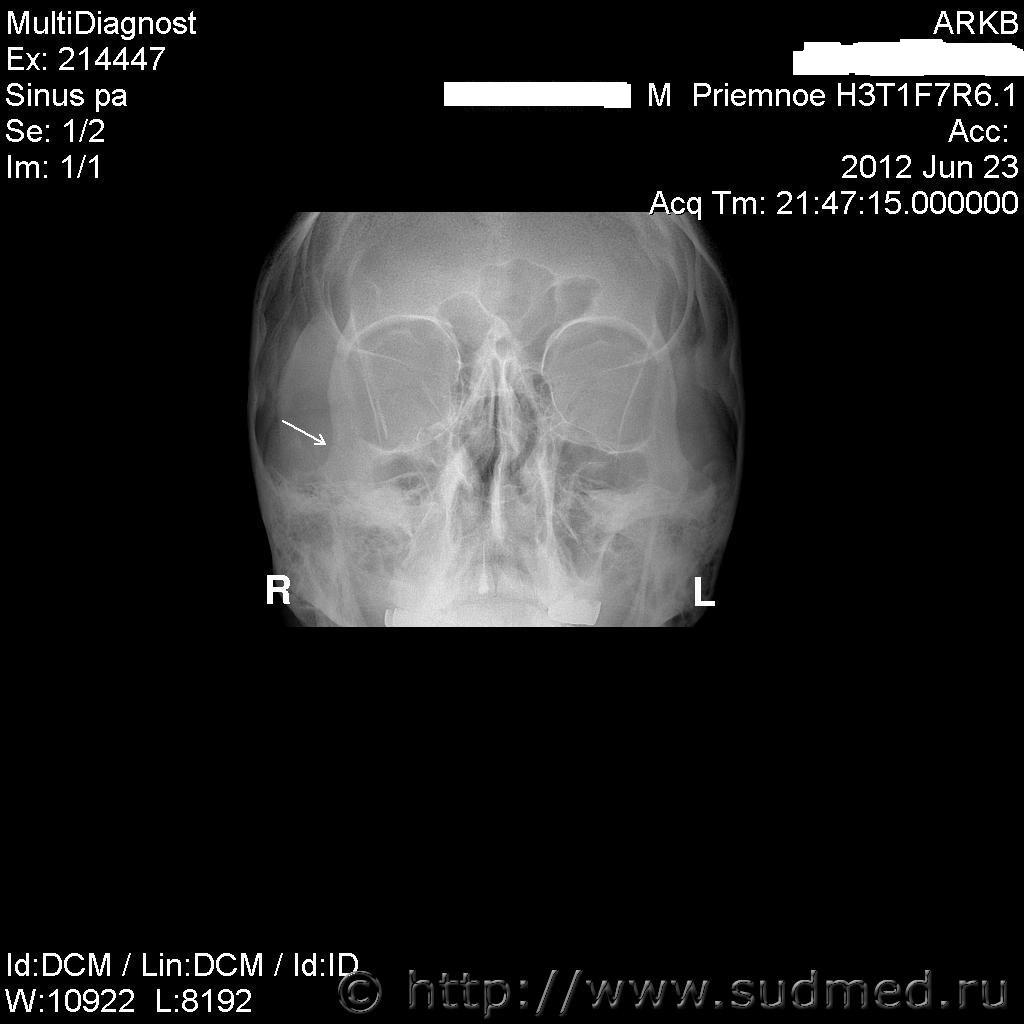

Выкладываю редактированные сканы ТС

Перелом скуловой кости виден на рентгенограммах. Кроме того, он подтверждается протоколом операции (открытая репозиция скуловой кости), т.е. врач непосредственно наблюдал линию перелома и репонировал (устанавливал в правильном положении) отломки кости. Есть фактическая продолжительность временной нетрудоспособности ("больничный") сроком на 47 дней. Этот набор фактов вполне позволяет обосновать длительное расстройство здоровья, что является квалифицирующим признаком вреда здоровью средней тяжести (согласно п.7.1 Приложения к Приказу Минздравсоцразвития от 24.04.08г. №194н). Если "повреждение тройничного нерва" (это не диагноз, а какой-то неясный намек на его возможность) привело к выраженному стойкому нарушению иннервации лицевой мускулутуры, т.е. сейчас лицо "перекошено", "отвисает" щека, опущен угол рта и т.п. - можно поставить в суде вопрос об обезображивании лица (см.ст.111 Уголовного кодекса РФ), если этого, на самом деле, сейчас нет - значит, нет. Все остальное - точно не больше среднего вреда (реально - меньше). "искривление перегородки носа,нестабильность шейных сегментов С3-С4,С4-С5,С5-С6" - это не травма, а индивидуальные особенности (для профилактики бесцельных вопросов: "раньше этого врачи не видели" и "раньше там не болело" - не аргумент, т.е. где-нибудь в суде можете так говорить, а здесь, на профессиональном форуме, это не нужно).